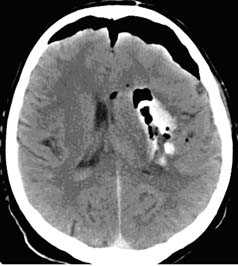

ЧМТ можно разделить на первичные и вторичные повреждения. Клинически это деление чрезвычайно важно, по причине того, что вторичные повреждения можно предотвратить. Вторичные поражения возникают как осложнение первичной травмы и неадекватно проводимой терапии. Клинически значимые травматические изменения, такие как субдуральная и эпидуральная гематомы, субарахноидальное кровоизлияние (САК) и геморрагические ушибы головного мозга, обычно, четко визуализируется при КТ. Однако есть повреждения головного мозга, которые сложно обнаружить с помощью КТ. В первую очередь к таким повреждениям относятся: диффузное аксональное повреждение (ДАП), базальные и стволовые ушибы головного мозга, а также ранний цитотоксический отек, как проявление вторичных ишемических изменений вещества мозга. Все эти состояния могут быть легко выявлены с помощью МРТ. Их обнаружение важно для установления причин ранее необъяснимого неврологического дефицита, а также для оценки долгосрочного прогноза. В настоящее время МРТ обычно используется для решения вопросов, которые не могут быть решены с помощью КТ, а не как как метод скрининга. Мы также часто исходим из этого принципа. Однако в последние годы нами рассматривается и, по мере возможности, применяется другой подход - использование МРТ как первичного и единственного метода диагностики острой ЧМТ у детей и последующем мониторинге за течением и лечением травматических повреждений. Это позволяет уже на этапе поступления ребенка в стационар выявлять все первичные и вторичные компоненты ЧМТ, более дифференцированно подходить к лечению проявлений травматической болезни головного мозга и, соответственно, потенциально улучшать прогноз исхода ЧМТ.

- выявить наличие внутричерепной гематомы (её характер, локализацию, размеры),

- выявить наличие очага ушиба головного мозга (его локализацию, размеры, характер, наличие геморрагического компонента),

- выявить субарахноидальное кровоизлияние,

- выявить внутрижелудочковую гематому,

КТ с внутривенным контрастированием (КТ-ангиография) по неотложным показаниям, как правило, не выполняется. Показанием к такому исследованию является обнаружение на нативных томограммых внутримозговых гематом, локализующихся в местах возможного разрыва аневнизмы.